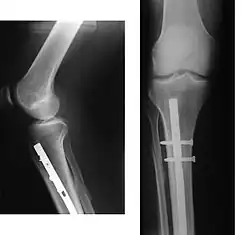

Schienbeinbrüche (Frakturen) kommen häufig vor. Sie werden mittels Metallplatten und Schrauben bzw. Marknagelungen operativ durch die so genannte Osteosynthese versorgt.